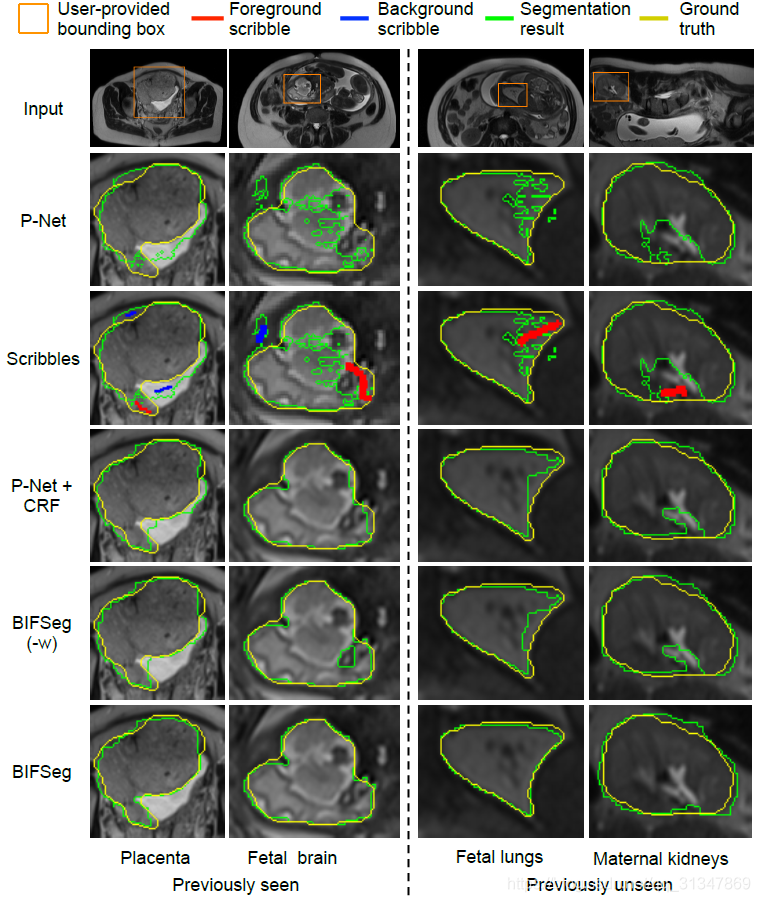

(3)Supervised Image-specific Fine-tuning:

有监督的微调需要用户在初始分割结果上画出分割不准确的地方,蓝线表示应该划分为背景,红线表示应该划分为前景。

同一个初始分割结果,同样的 scribbles,对比三种调整方法,虽然都有效果上的提升,但依然发现是 BIFSeg 的分割结果最好。